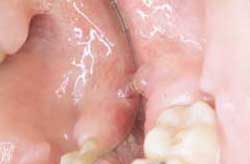

Paciente femenina de 47 años de edad, acude a consulta por presentar una lesión de aproximadamente de 10 milímetros de diámetro, ubicado en la cara interna del maxilar inferior lado derecho, hacia la encía libre, la cual tiene forma de vesícula, cuyo contenido es un líquido transparente, de base de implantación sésil, indoloro y de 4 meses de evolución. Al interrogatorio la paciente refiere que la lesión tiende a romperse cuando ingiere alimentos duro, pero luego vuelve aparecer al cabo de pocos días. No presenta antecedentes generales contributorios. Se da un diagnóstico clínico provisional de mucocele, se le indicaron los exámenes de laboratorio con el fin de realizar la biopsia; una vez hecha ésta el diagnóstico definitivo resultó: mucocele. (Foto nº 1)